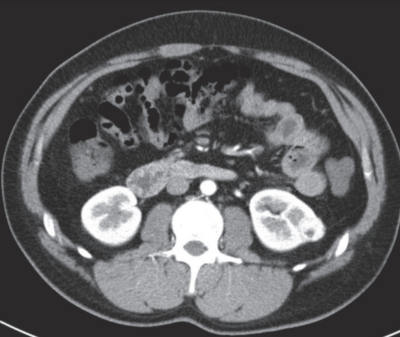

尿所見:蛋白(−)、糖(−)、ケトン体(−)、潜血+、沈渣に異常を認めない。血液所見:赤血球551万、Hb 14.8g/dL、Ht 45%、白血球5,600、血小板22万。血液生化学所見:総蛋白 7.3 g/dL、アルブミン 4.8 g/dL、総ビリルビン 0.9 mg/dL、AST 18 U/L、ALT 24 U/L、LD 179 U/L(基準 120~245)、尿素窒素 11 mg/dL、クレアチニン 0.9 mg/dL、尿酸 4.9 mg/dL、血糖 103 mg/dL、Na 143 mEq/L、K 4.2mEq/L、Cl 105 mEq/L、Ca 9.1 mg/dL。腹部造影CTを別に示す。胸部CT、骨シンチグラフィーで異常を認めない。

治療について適切なのはどれか。

b. 腎部分切除術